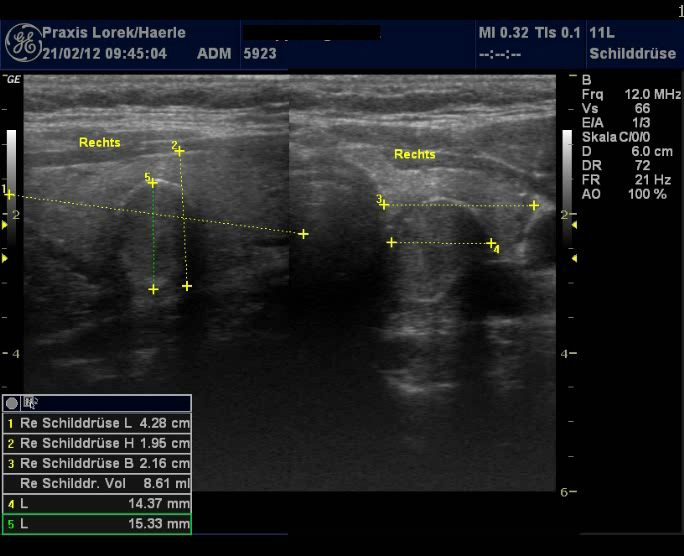

| Abb. 1 und 2:

Ungleichmäßige Echoarmut der Schilddrüse bei einer

31-jährigen Patientin, Schilddrüse mit etwa 8,8 ml etwas unterhalb

des Normbereichs, eher atrophische Verlaufsform (Ord-Thyreoiditis), Zufallsbefund

2008, es werden keine Symptome angegeben. Keine Knoten. |